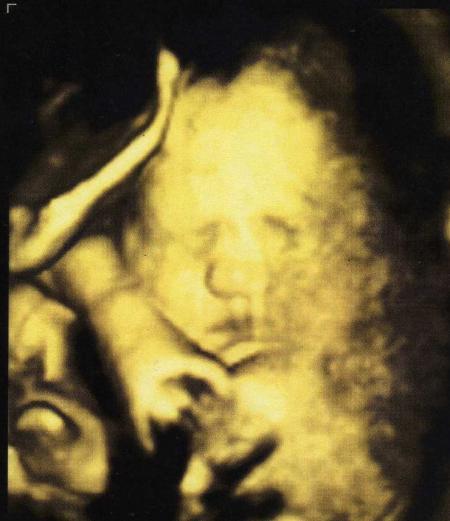

Hallo Mädels, Daumen drücken hat geholfen...mit meinen beiden ist alles suuper...:-) Keinerlei Rhythmusstörungen zu finden... beide sind auch super gewachsen und wiegen schon über 2000g... Habe noch zwei wunderschöne Bilder dazu bekommen...das erste ist von der kleinen Maus, das zweite vom Brüderchen...zum verlieben..